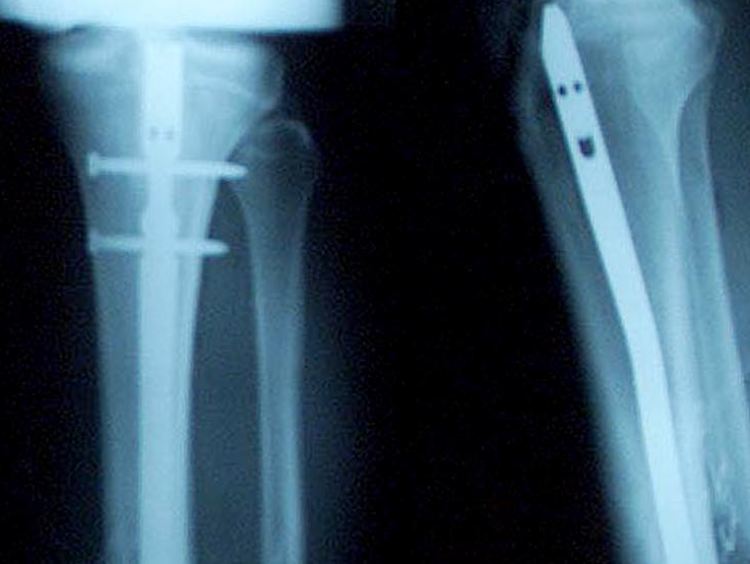

Es sollte nur dann geröngt werden, wenn auf anderem Weg keine eindeutige Diagnose möglich ist.

(Foto: REUTERS)